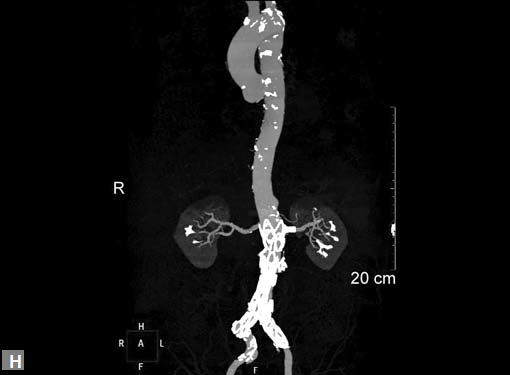

Figs 19A to Y (A to C) Scannogram (A), plain (B) and contrast study (C) show partial anomalous pulmonary venous connection; (D to F) Heterotaxy; (G) Aortic occlusion; (H and I) Aortic stents; (J) Aortic dissection with ‘Benz’ sign due to second dissection within the true lumen; (K, L and M) Aortic dissection with thrombus in pseudolumen following catheter angiogram; (N) Aortic dissection involving common carotid arteries and subclavian artery; (O, P, Q and R) Aortic dissection with right renal artery arising from true lumen and left renal artery from false lumen; (S, T, U and V) Stanford B dissection with extension Y to iliac vessels; (W to Y) Aneurysmal dilation of ascending aorta